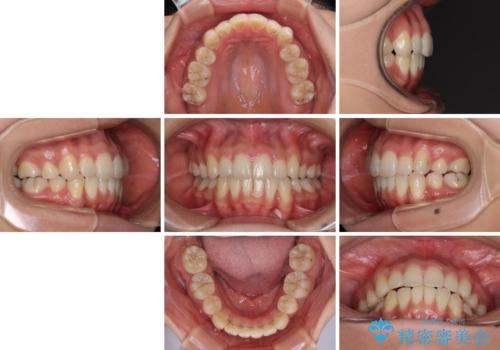

目安の装着時間である1日22時間をしっかりと実践してくださり、半年強という短期間で治療を終えることができました。